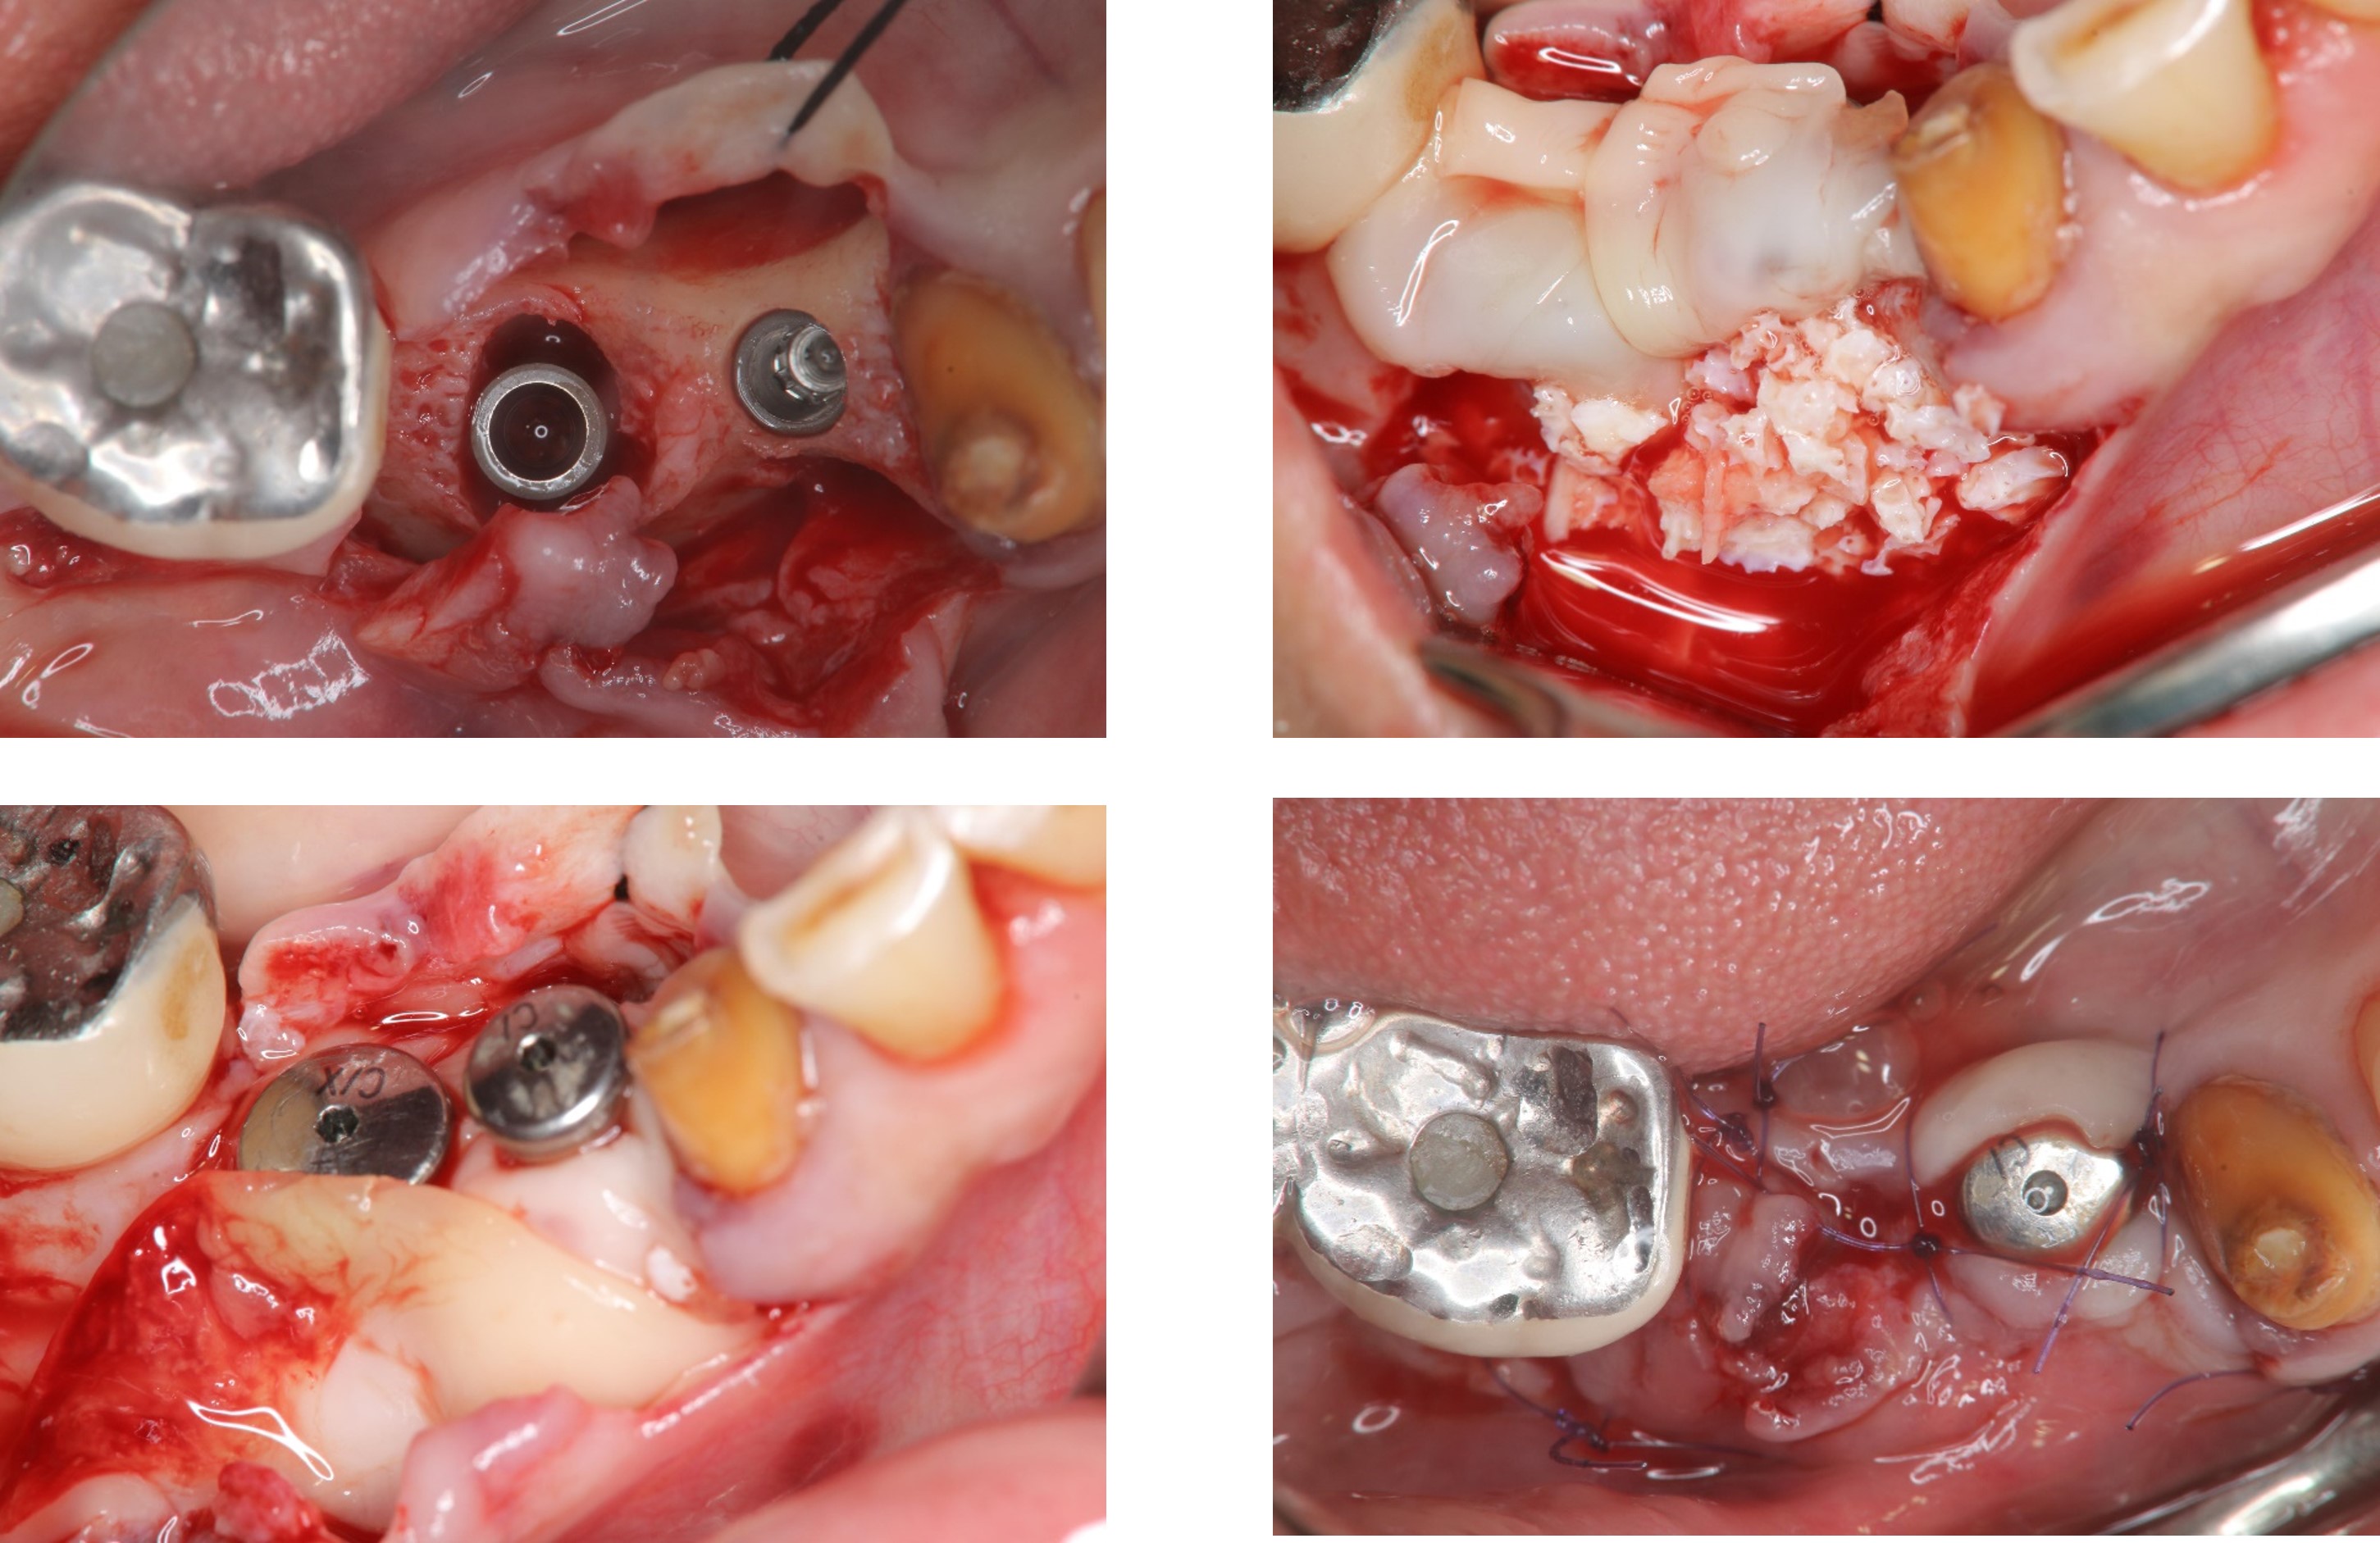

植體植入與補骨